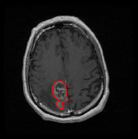

We argue that the sub-optimal paradigm of processing different abstractions within a single CNN pipeline can be remedied through the effective processing of information in a structured manner. Consequently, we devise strategies for disentangling the edge and texture information within a single training pipeline. Figure 2 illustrates how our proposed module, dubbed EG-CNN, can be paired with any existing CNN encoder-decoder to improve segmentation quality near intensity edges. We have applied our EG-CNN to the tasks of brain and liver tumor segmentation in medical images (Figure 3).

(1) Brain MR (2) Liver MR (3) Liver CT (4) Lung CT